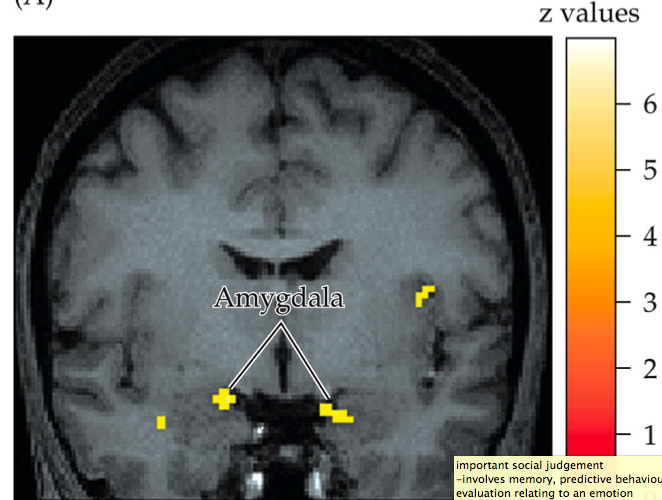

What part of the brain is activated during judgments of trustworthiness?

What neural substrates mediate social cognition?

-internalisation and learning of rules -linked to affective experiences -ventral and medial prefrontal cortex -sub cortical structures (medial dorsal thalamus, amygdala) (emotions motivate us= make us do what we should do, rule following and what it feels ike medial prefrontal cortex and subcortical structures= amygdala and medial dorsal thalamus)

What are the main centers of social cognition?

-ventral and medial prefrontal cortex -sub cortical structures (medial dorsal thalamus, amygdala)